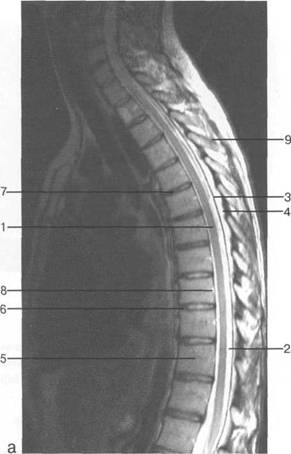

отдел

хвост

I intumescentia

lumbalis; radix n.

spinalis

(Th. XII); costaXII; conus

medullaris;

vertebra L.

I; radix; ramus

ventralis n.spinalis (L. I); ramus

dorsalis

n.spinalis (L. I); - filum

terminale;

ganglion

spinale (L.III);

I1 - vertebra L V; ganglion spinale

(L.V); os sacrum; 14 - N. S. IV; 15 -

N. S. V; 16 - N. coccygeus; filum

os coccyges.

fossa rhomboidea; pedunculus cerebellaris sup.; pedunculus cerebellaris medius; n. trigeminus; n. facialis; n. vestibulocochlearis; margo sup. partis petrosae; pedunculus cerebellaris inf.; tuberculi nuclei cuneati; tuberculi nuclei gracilis; sinus sigmoideus; n. glossopharingeus; n. vagus; n. accessories; n. hupoglossus; processus mastoideus; N.C. I; intumescentia cervicalis; radix dors.; ramus ventr. n. spinalis IV; ramus dors. n. spinalis IV; fasciculus gracilis; fasciculus cuneatus; ganglion spinale (Th. I).